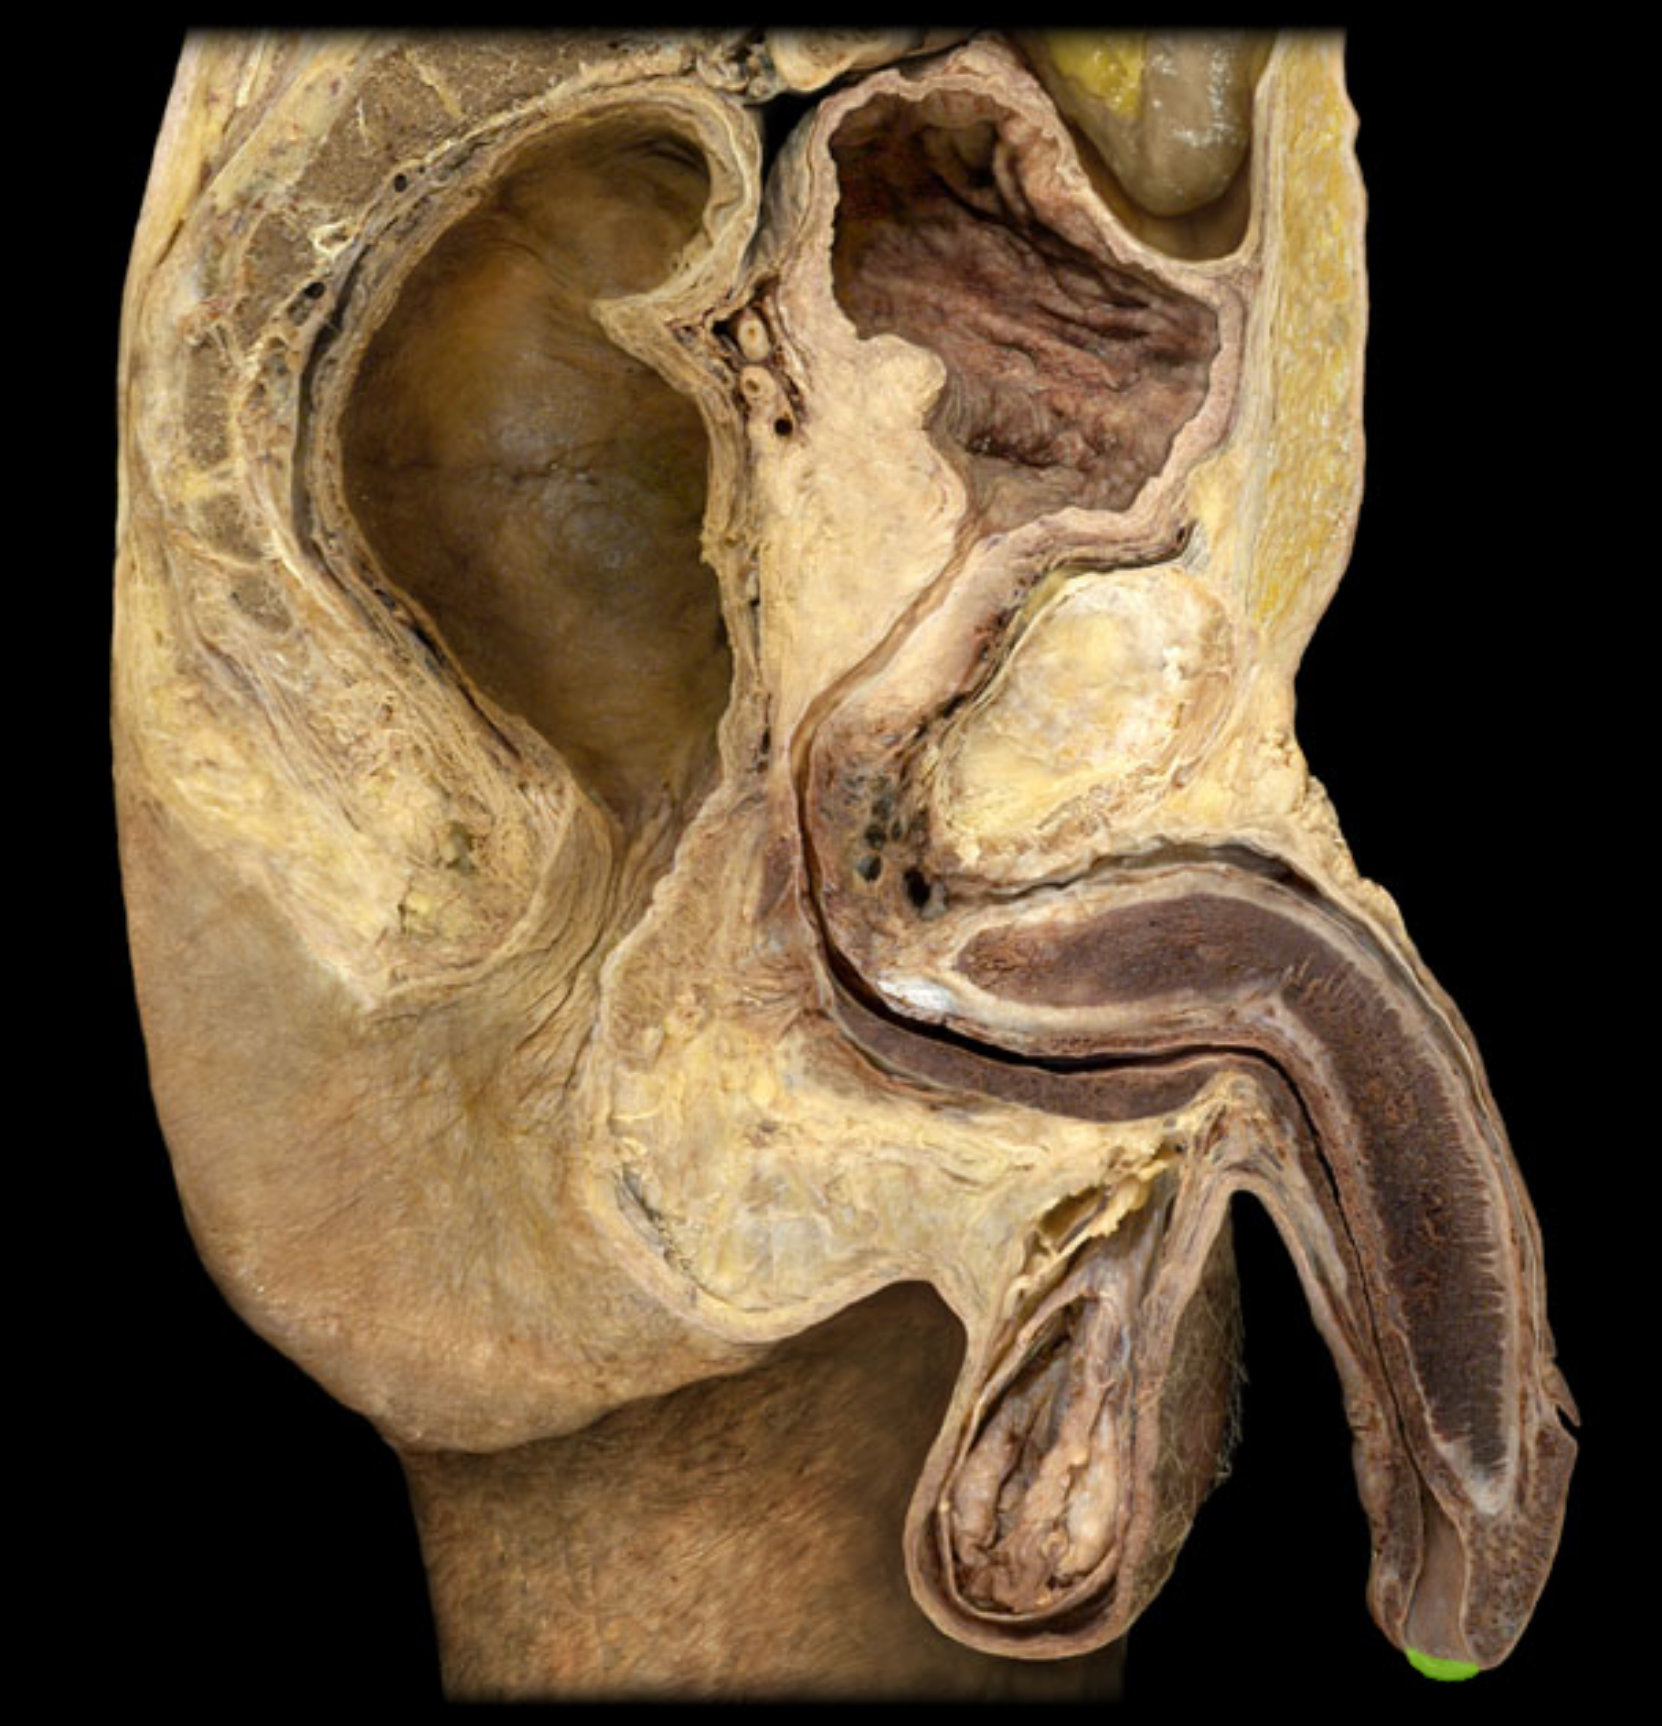

Vas deferens (ductus deferens)

Ejaculatory duct

Seminal vesicle

epididymis